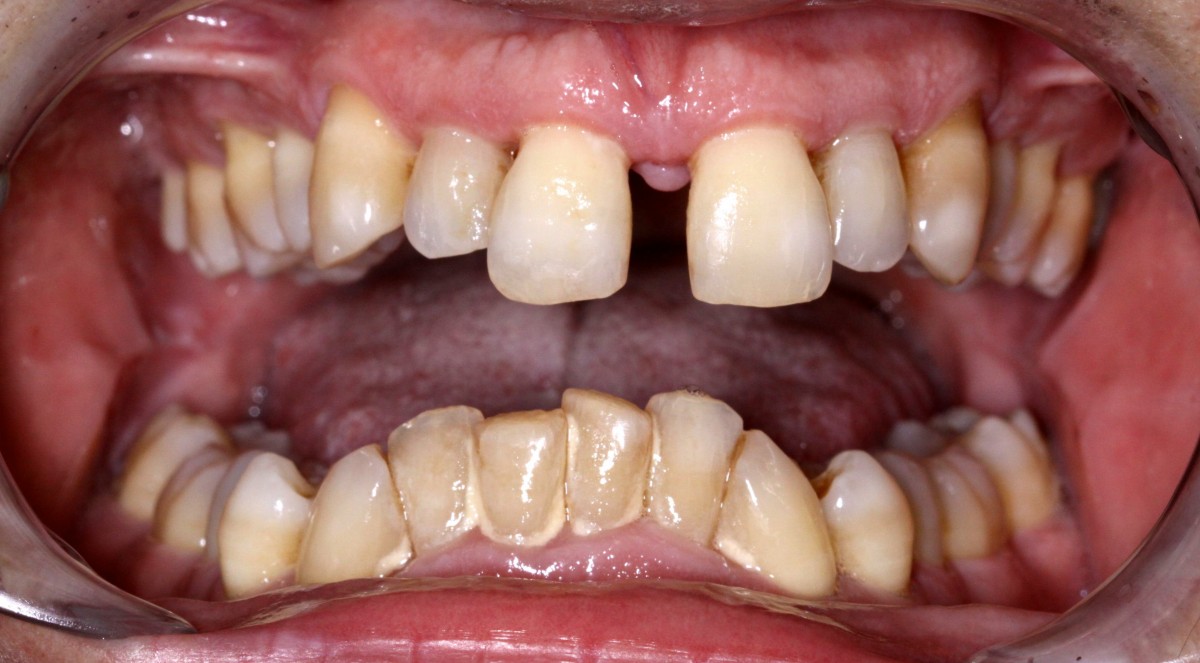

G.L., 51 years old patient, pre- sented to the clinic with Class I malocclusion, deep bite with complete coverage of lower in- cisors, big median diastema between teeth #11 and #21, lack of interdental papilla and poor oral hygiene (figs. 3, 4).

Lower incisors erupted verti- cally and created 2 planes of occlusion and exaggerated curve of spee in the lower arch. The upper lip “pushed” the an- terior incisors lingually and consequently the bite was deepened. Oral hygiene is poor mainly due to the crowding of the lower incisors. The upper diastema resulted in the loss of the interdental papilla between the central incisors (figs. 5, 6).

Patient had gone through pre- vious orthodontic treatment

with extraction of upper first premolars (#14, #24). Space between #11-#21 is slowly opened during the years and space start to develop distally to the upper lateral incisors. Lower incisors are hitting traumatically the palate creat- ing proliferation of the epithe- lium and constant inflamma- tion. Lower anterior crowding is around 4.5 mm (#33-#43) (figs. 7, 8).